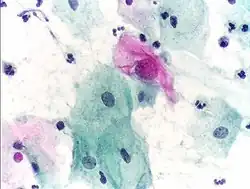

Micrograph of a normal pap smear -

Micrograph of a Pap test showing trichomoniasis. Trichomonas organism seen in the upper right. Pap stain. -